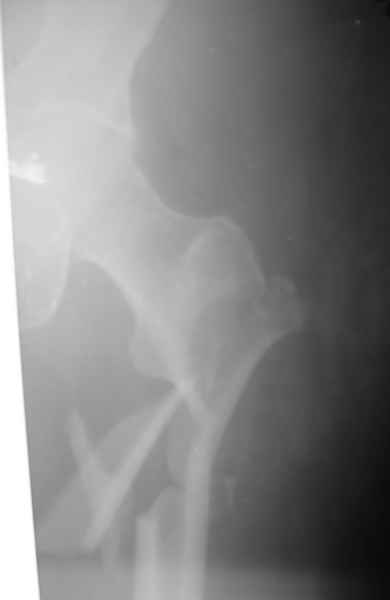

Современная генерация бедренных гвоздей ChM позволяет "перекрыть" все бедро. Почему "правый гвоздь на левое бедро"?

Я бы поставил слева любой проксимальный гвоздь. Подойдет и стандартный СhM в "реконструктивном" варианте. А справа - хоть антеградно, хоть ретроградно - кому что нравится. Я бы колено сверлить не стал. Ввел бы в дистальный отломок 3-4 винта обязательно в 2-х плоскостях.